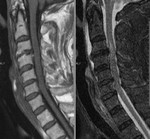

[画像診断]2010-10-08に提示した症例のMRI(頚髄損傷) 2010-10-10